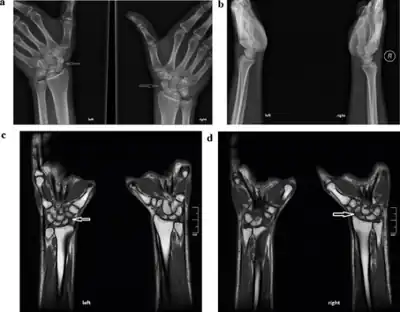

a,b) Radiography of bilateral stress fracture of the carpal scaphoid c,d) MRI of left and right carpal scaphoid stress fracture

X-rays usually do not show evidence of new stress fractures, but can be used approximately three weeks after onset of pain when the bone begins to remodel.[4] A CT scan, MRI, or 3-phase bone scan may be more effective for early diagnosis.[7]

MRI appears to be the most accurate diagnostic test.[8]